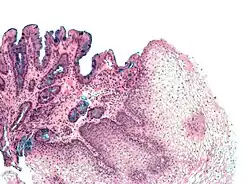

A metaplasia do esôfago de Barrett é bastante visível através da endoscopia digestiva alta. No exame pode ser notada uma lesão de "cor salmão" ou "cor vermelho-róseo". O médico que realiza o exame endoscópico recolhe amostras da lesão esofágica (biópsia).

Estas amostras são analisadas sob microscópio para determinar se as células são de natureza gástrica ou intestinal[5]. A metaplasia intestinal do esôfago de Barrett é geralmente identificada com a ocorrência de células caliciformes no epitélio. A presença das células metaplásicas intestinais é necessária para que o diagnóstico da doença seja confirmado.

Biópsia

O esôfago de Barrett é caracterizado por uma modificação no epitélio do órgão. Na doença, ocorre a presença de epitélio colunar na porção inferior do esôfago, substituindo o epitélio escamoso normal do esôfago. Esta transformação do epitélio é um exemplo de metaplasia. Apesar de o epitélio colunar ser capaz de suportar melhor a ação erosiva das secreções do estômago; esta metaplasia confere um risco aumentado de câncer no esôfago do tipo adenocarcinoma.[6]

As células colunares metaplásicas podem ser de dois tipos: gástricas (similares às do estômago, que não são tecnicamente um esôfago de Barrett) ou intestinais (similares às células dos intestinos). Uma biópsia da área afetada geralmente irá apresentar uma mistura de ambos os tipos. A metaplasia intestinal confere um risco maior de malignidade.